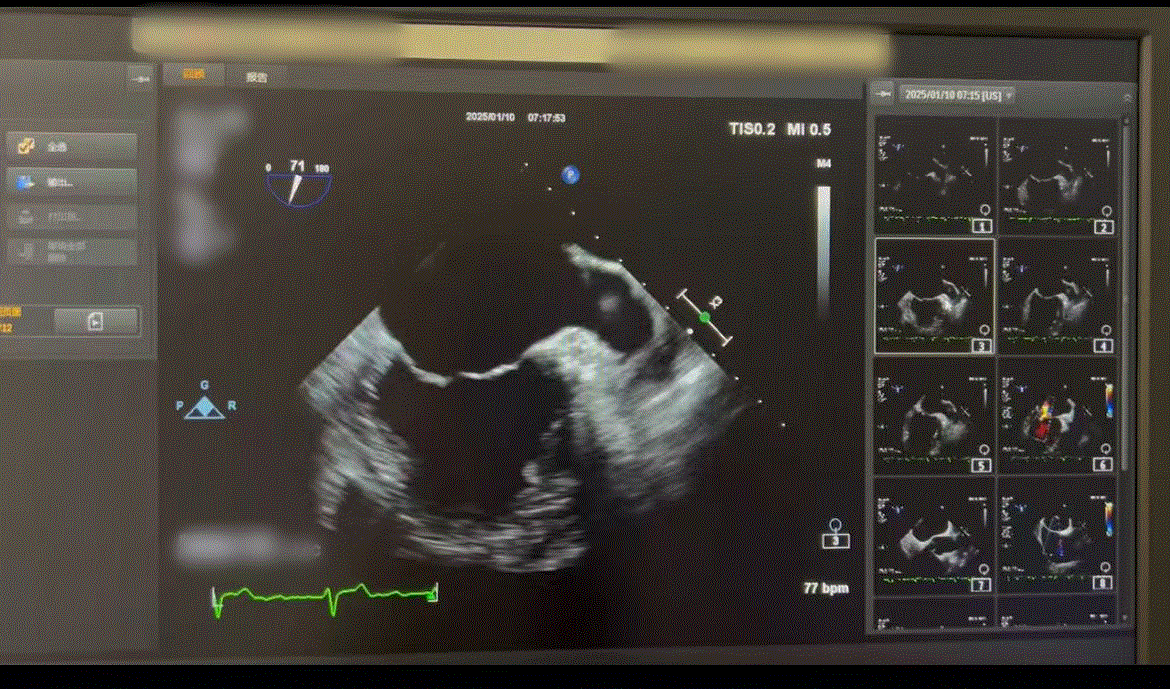

清晰显示二尖瓣、主动脉瓣等瓣膜的形态、厚度、启闭情况,准确判断瓣膜狭窄或关闭不全的程度,为手术方案的制定提供关键依据。

对房间隔缺损、室间隔缺损、动脉导管未闭、卵圆孔未闭等先天性心脏病的微小缺损,以及复杂畸形的细节,具有极高的检出率。尤其是对卵圆孔未闭更有优势。